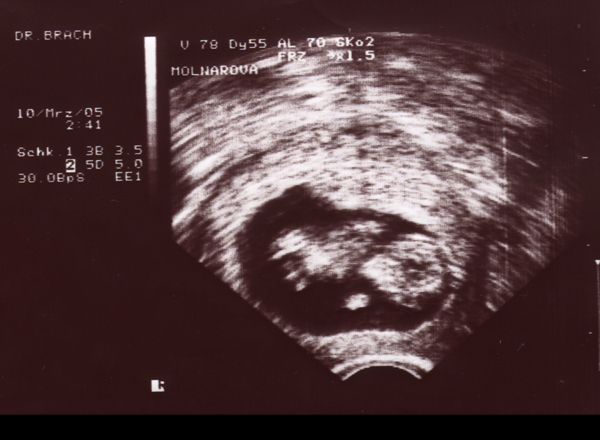

22.04.05 - 07. Woche - 0,7cm

09.05.05 - 10. Woche - 2,0cm